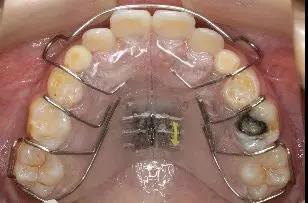

微信图片_20200210130923

(5)上颌合垫式乳牙反合矫治器加力者:若无法按时复诊,建议继续佩戴矫治器但不能自行加力。

微信图片_20200210130926